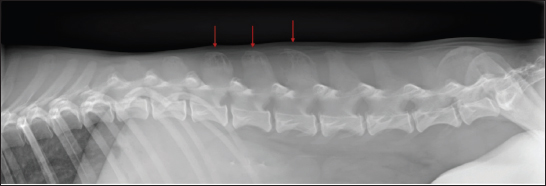

Fig. 2. Soft tissue window sagittal reconstruction of the head (A) pre-contrast and (B) post-contrast administration, showing the contrast-enhancing extra-axial lesion affecting the sphenoid bone (red arrows). Lateral thoracic and lumbar radiographs were performed to localize any additional osteolytic foci due to the multifocal hyperesthesia. Polyostotic radiolucent moth-eaten lesions were observed at the L1, L2, and L3 dorsal processes (Fig. 3). Subsequently, an abdominal ultrasound was performed, showing heterogeneous echogenicity of the spleen and liver parenchyma and enlarged iliac lymphatic nodules. Fine needle aspirates were obtained from the vertebral lesions, spleen, and liver. The cytological evaluation of the bone lytic lesions revealed a mixed inflammatory cellular population predominantly composed of macrophages, plasma cells, lymphocytes, and non-degenerated neutrophils. Intracytoplasmic structures compatible with parasitic forms of Leishmania spp. (amastigotes) were observed inside macrophages (Fig. 4). The same structures were observed in the spleen and liver, along with extramedular hematopoiesis. Based on the previous results, a proteinogram revealed monoclonal gammopathy. An Enzyme-Linked Immunosorbent Assay anti-body anti-leishmania serology resulted in a high seropositive result, 4.93 (R.R: 0–0.9).

Fig. 3. Laterolateral radiograph of the caudal thoracic and lumbar spine. Polyostotic radiolucent moth-eaten lesions were visible in the dorsal processes of L1, L2, and L3 (red arrows).